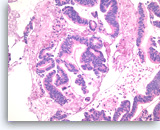

Ductal adenocarcinoma #3,

Pancreas FNA, Cell Block.

The tumor cells form glandular structures with focal loss of cell polarity and stratification. There are also scattered single and small groups of tumor cells. Intracytoplasmic mucin is seen in some of the tumor cells. Note extracellular mucin (right edge) and a background of necrotic cellular debris.

40X

Ductal adenocarcinoma #3,

Pancreas FNA, Cell Block.

The tumor cells form glandular structures with focal loss of cell polarity and stratification. There are also scattered single and small groups of tumor cells. Intracytoplasmic mucin is seen in some of the tumor cells. Note extracellular mucin (right edge) and a background of necrotic cellular debris.

40X